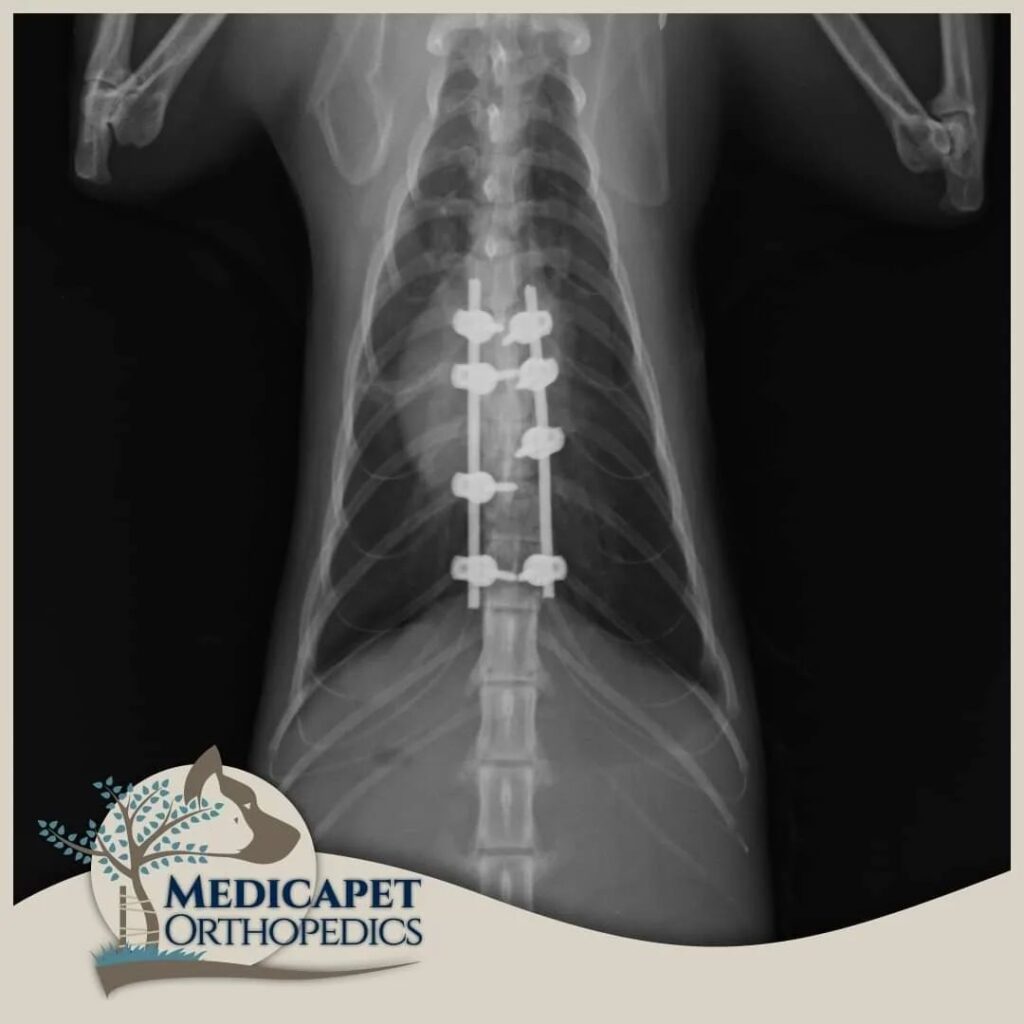

omurga cerrahisi

omurga kırıkları, disk fıtığı gibi olgularda acil müdahale başarı şansını yüksetir.

zaman geçtikçe kalıcı felç olasılığı artar.

zaman geçirmeden bize ulaşın

Kliniğimizde karşımıza çıkan sinir sistemi hasarlı hastaların pek çoğu bu hasarı bazı kazalar

sonucunda almış olarak geliyorlar. Trafik kazaları, yüksekten düşmeler, insan saldırısı, başka bir

hayvanın saldırısı gibi olayların sonucunda özellikle omurgada kırıklar, kırık bulunmayan omurga

travmaları, kafatası hasarları, kol – bacak ve kalça kırıklarına bağlı geçici ya da kalıcı felç durumları

gibi durumlar en sık tedavi ve opere ettiklerimizin başında geliyor. Öte yandan bazı ırkların genetik

yatkınlıkları da omurga problemlerine yol açabiliyor.